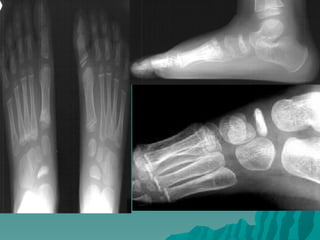

Köhler Hastalığı:

  Naviküler kemiğin osteokondrozudur.

Kemik üzerine gelen tekrarlayıcı

kompresyon güçlerinin rolü olduğu

düşünülür.

 Olguların %75’i erkek çocuklarda ve en

sık olarak beş yaş çevresinde görülür.

Bilateral olabilir.

 Naviküler kemik üzerinde ağrı ve

duyarlılık ve şişlik olur. Radyolojik olarak

naviküler kemikte düzleşme, düzensizlik

ve skleroz görülür. Tedavide, ağrılı

dönemde alçı yapılabilir, daha sonra

tabanlık verilir. Yaklaşık altı ayda hastalık

kendiliğinden geçer.

Freiberg Hastalığı:

 Metatars başlarının osteokondrozudur. En

çok ikinci metatars başında görülür.

Bilateral olabilir. %75 oranında kızlarda ve

adolesan çağda görülür.

 Hastalık metatarsaljiye neden olur.

hareket kısıtlılığı olur.

 Radyolojik olarak metatars başında

yassılaşma, düzensizlik ve skleroz görülür.

 Ağrılı dönemde alçı yapılır daha sonra

ayakkabının içine metatars yastığı

uygulanır.

 yakınmalar sürüyorsa, metatars başı

rezeke edilebilir.